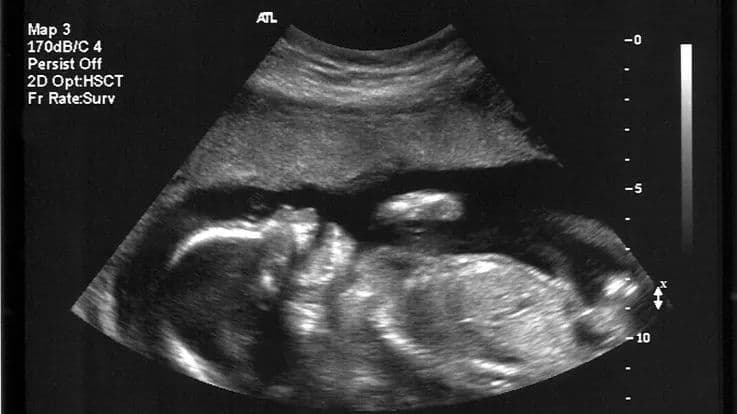

PGT-P is a technique which can help prospective parents achieve all that through polygenic testing. Thuy and Rafal are the first of a couple of biotech firms in the US to open up genetic screening services to prospective parents. They are the mum and dad of Aurea, a little girl who represents a significant first in undergoing genetic testing as an embryo to screen for a disease. She is the world’s first PGT- P baby, where PGT-P stands for Preimplantation Genetic Testing for Polygenic disorders . This could possibly mean she is statistically less likely than any of us to develop a genetic disease or a disorder throughout her life. This technique allows prospective parents to actively select their own embryos, based on the strength of its genes. It examines the embryos during in vitro fertilization (IVF) before possible transfer to a woman’s uterus for a range of genetic problems that can cause implantation failure, miscarriage and birth defects in a resulting child. Embryos found to have such flaws are excluded from being transferred to the mother’s womb for a pregnancy.